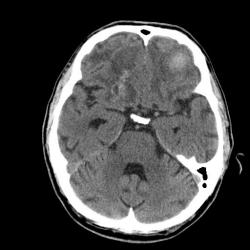

2-я - через 26 дней контрольное иследование.

Меня насторожила картина и я порекомедновала с контр. усилением.